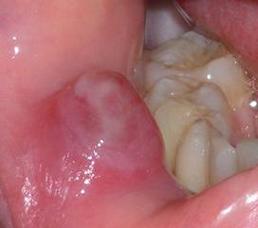

(图片来源网络,侵删)